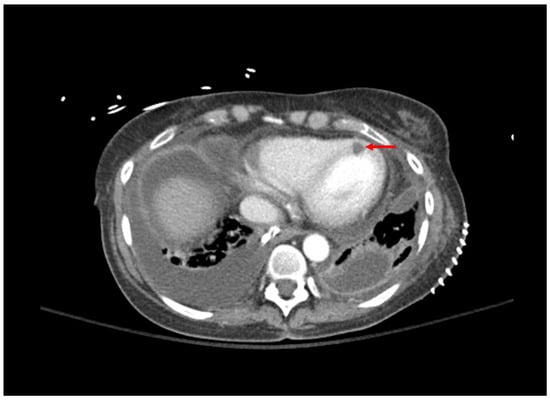

| 1: Aspergillosis | 53 YO, 5 weeks post-transplant. Received antithymocyte globulin and carfilzomib 2 weeks prior. Symptom of desaturations. |

Chest CT: small right basilar empyema, partial collapse of left lower lobe, bilateral ground glass opacities, and septal thickening (Figure 1). Chest and pleural tissue culture from decortication procedure: A. fumigatus. |